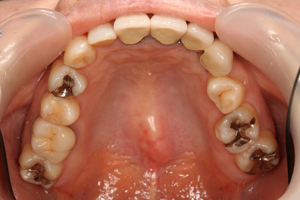

■口の中の金属を白くする症例

初診時